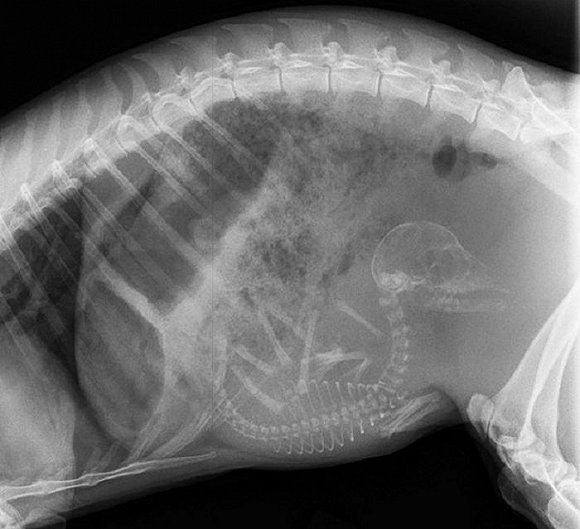

可爱又毛骨悚然 怀孕动物的X光片

人类之间分享母亲肚子里胎儿的X光片是一件非常常见的事情,但是,纵使你觉得自己对X光片已经见怪不怪,在看到了下面这些怀孕动物的X光片后你仍旧会说"哦我的天哪"。

自然总是充满有趣事实,你是否知道在各种怀孕的动物中负鼠的生育速度最快?它们只需要14天就可以分娩,而雌性大象的怀孕时间则长达23个月。现在 吉尼斯世界记录上记载的一次分娩中最大小狗出生数量为24只,而海马的生殖则由雄性负责,一只雄性海马每次平均产出200只幼鱼苗。

以下就是一些动物在怀孕时的X光片。

4. 猫